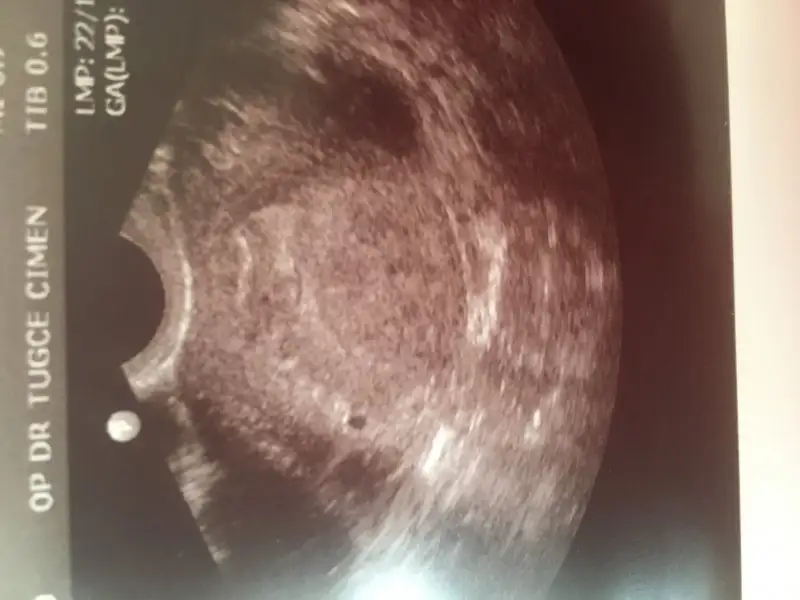

şimdi ilk resim şu 5+4 gittim değer 1112 idi , doktor dediki keseye benzer bişi var. ama bunu raporunda kist olarak değerlendirmiş ve bana resmen fitili attı dış gebelik şüphelisin diyerekten 1 hafta nasıl geçti bilmiyorum

şimdide 6+4 gittiğim doktor bunu verdi dediki sandıgınız kadar buyuk bı gebelık degıl bu dedı. cok saglıklı gozukuyor dedı ayrıca 5+4 tekı doktorun raporund asoyle yazıyordu

Bilemiyorum şimdi ne olacak dahada doktora cok var. ayrıca doktor 10 gun sonra kalp atıslarına gel dedı. bu kadarda net . Sızın kese nasıl